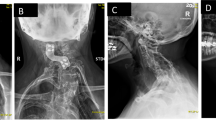

Study design: Case study on a 45-year-old female with progressive weakness and paresthesias in her lower extremities and a magnetic resonance image of an intramedullary mass at the level of C5–6 and a Klippel–Feil (KF) deformity ventral to the lesion.

Objective: Present an interesting case of an intramedullary mass coexisting with a ventral KF deformity with review of the medical literature on intramedullary masses and cervical spine biomechanics.

Results: The patient underwent open neurosurgical excisional biopsy of the intramedullary mass which revealed a non-neoplastic inflammatory mass that slowly resolved with medical management.

Conclusions: While no definitive etiology was found in this case we offer two interesting mechanisms: (1) maldevelopment of the cervical spine or (2) this inflammatory mass is in response to an abnormal motion at the level of the Klippel–Feil.